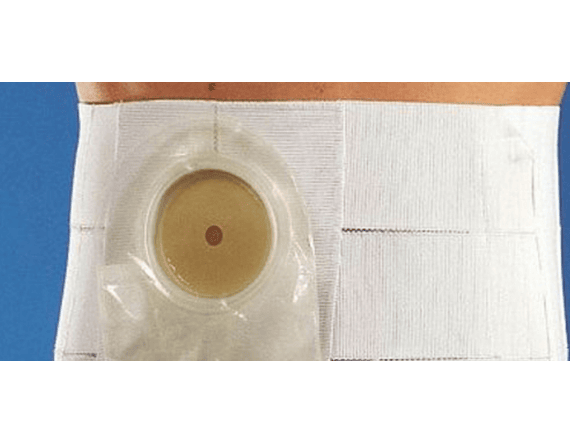

Faja de 2 bandas para colostomía, confeccionado con bandas de elástico libre de látex más orificio reforzado en elástico y ajustable con cierre de contacto.

Fijación de la bolsa de colostomía, prevención de hernia incisional (Protuberancia de tejido u órgano a través de una cicatriz quirúrgica en la pared abdominal)